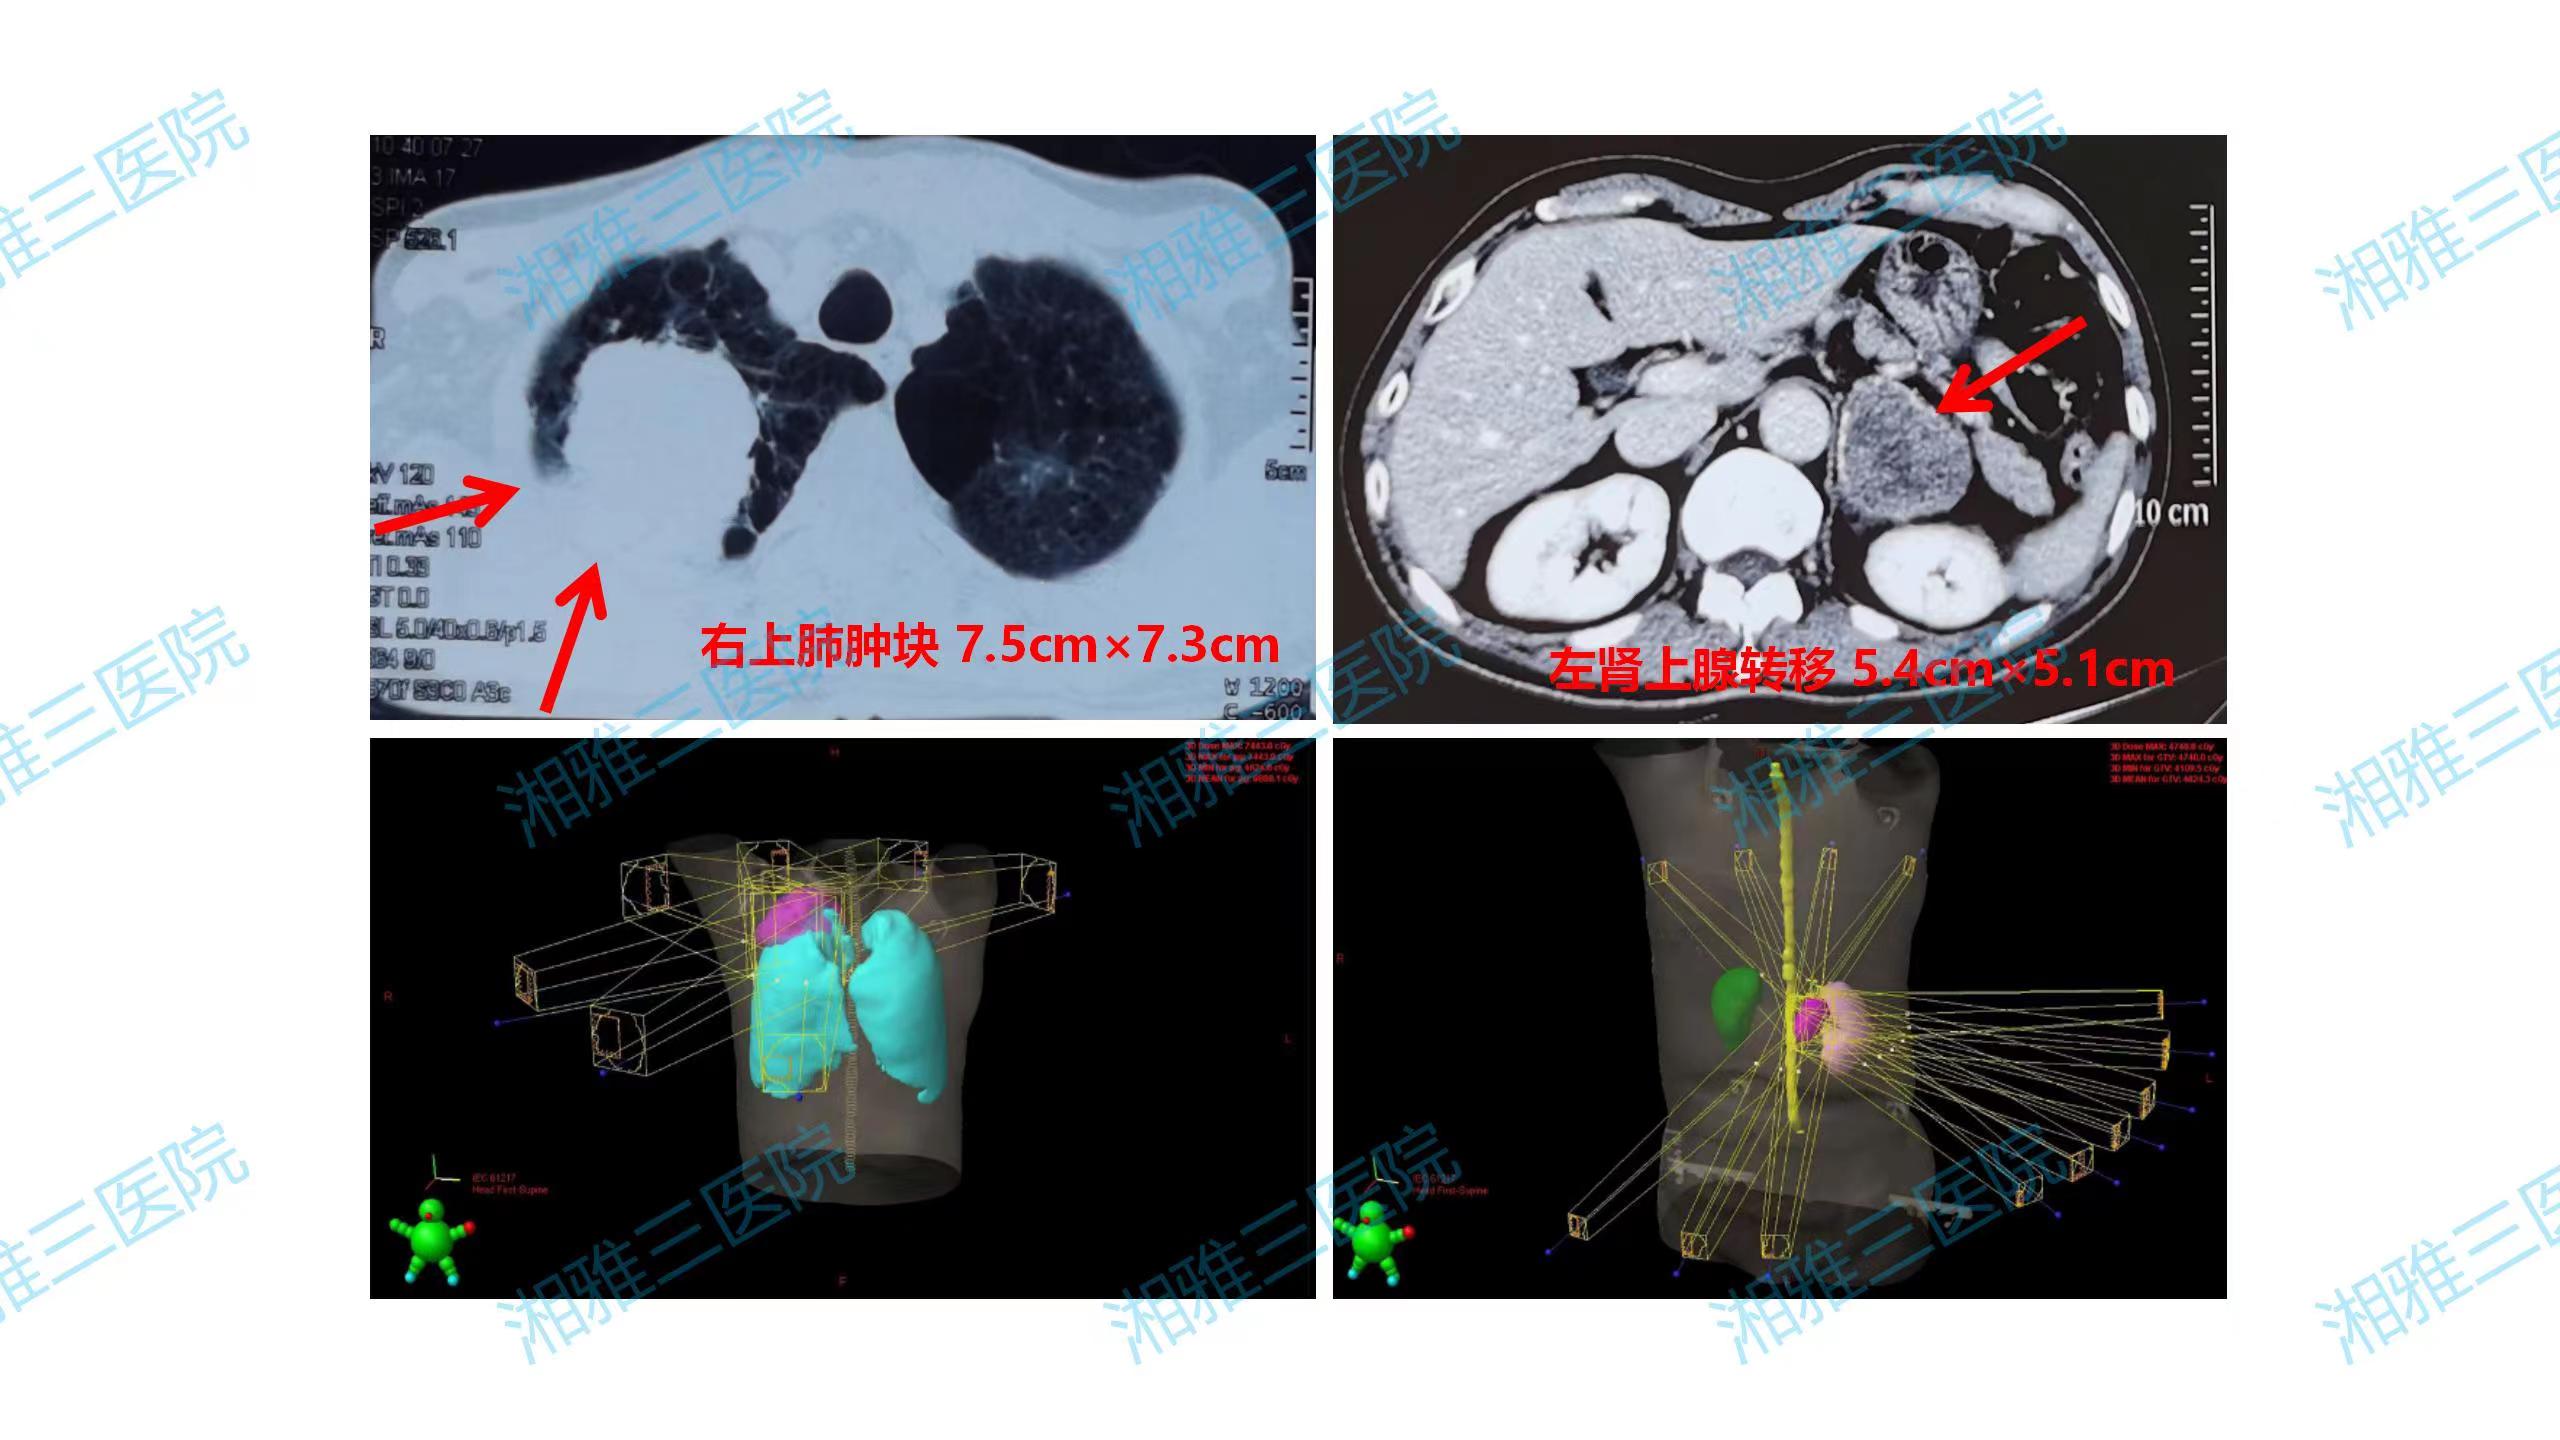

胸部肿瘤专科团队为患者组织了多学科联合诊疗(MDT),由肿瘤科、胸外科、放射科、病理科专家团队为刘叔叔进行病情评估并制定了个体化治疗方案:全身系统药物治疗+右上肺原发灶及左肾上腺局部治疗(手术或精确放疗),系统药物治疗选择了含铂双药化疗联合免疫治疗。

2020年7月,经过2周期系统药物治疗后,刘叔叔胸痛症状基本消失,影像学评估示肿瘤显著缩小。因右上肺肿块侵犯第1、2肋骨,手术创伤过大,经MDT讨论评估及刘叔叔和家属要求,不考虑手术切除,施行右上肺原发灶IMRT放疗,同步完成第3-4周期化疗联合免疫治疗。完成4周期化疗联合免疫治疗及原发灶放疗后,刘叔叔接受了培美曲塞联合免疫维持治疗。2020年10月接受了左肾上腺转移灶切除术,术后刘叔叔继续规律接受培美曲塞联合免疫维持治疗。然而,2021年5月复查提示左侧肾上腺转移灶复发。刘叔叔哽咽着回忆:“当时我自己都快放弃了,这个病反反复复估计是好不了,但是刘教授还是没有放弃让我彻底治好的机会。”经治疗组讨论,刘叔叔于2021年6月接受左肾上腺术后转移灶的SBRT放疗,放疗后继续接受培美曲塞联合免疫维持治疗,2022年3月开始减掉化疗,接受免疫单药维持至今。整个治疗期间多次复查,肺部及肾上腺转移灶均控制良好。

图2. 刘叔叔治疗前的CT显示右上肺原发性肺癌伴左侧肾上腺转移,经全身系统药物治疗缩小肿瘤后完成了两个区域的高精度放射治疗